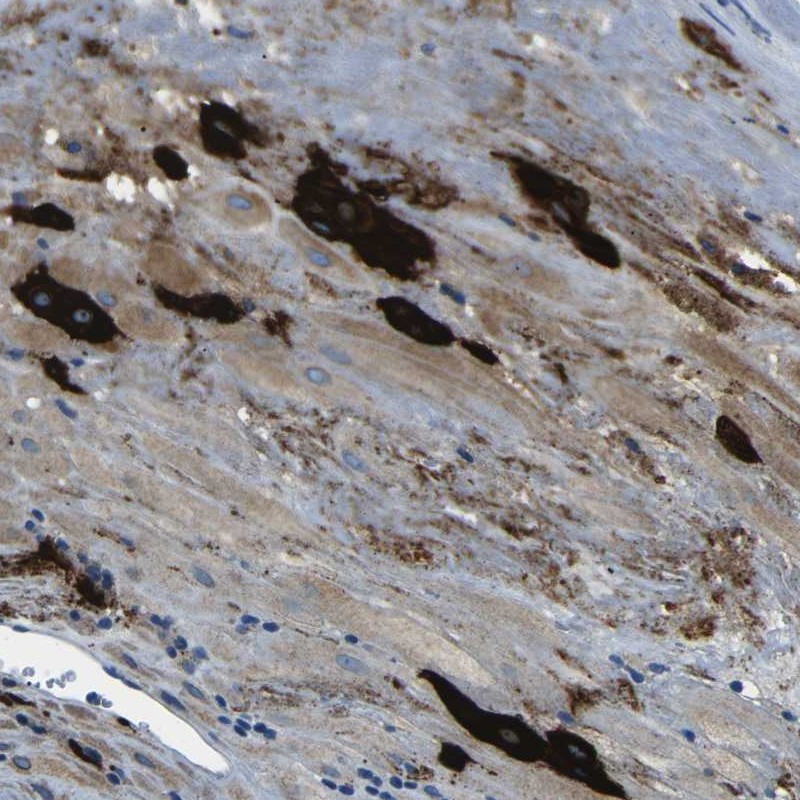

Supportive validation

- Experimental details

- Immunohistochemical staining of human placenta shows distinct cytoplasmic positivity in decidual cells.

- Validation comment

- Staining pattern partly consistent with experimental and/or bioinformatic data.